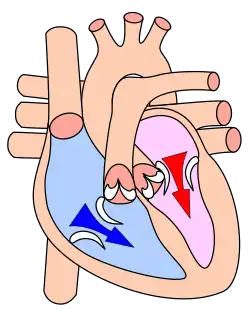

Diastole

The heart in the diastole phase. Cardiac Diastole is the period of time when the heart relaxes after contraction in preparation for refilling with circulating blood. Ventricular diastole is when the ventricles are relaxing, while atrial diastole is when the atria are relaxing. Together they are known as complete cardiac diastole. It should be noted that even this relaxation is an active, energy-spending process. During ventricular diastole, the pressure in the (left and right) ventricles drops from the peak that it reaches in systole. When the pressure in the left ventricle drops to below the pressure in the left atrium, the mitral valve opens, and the left ventricle fills with blood that was accumulating in the left atrium. Likewise, when the pressure in the right ventricle drops below that in the right atrium, the tricuspid valve opens and the right ventricle fills with blood that was in the right atrium